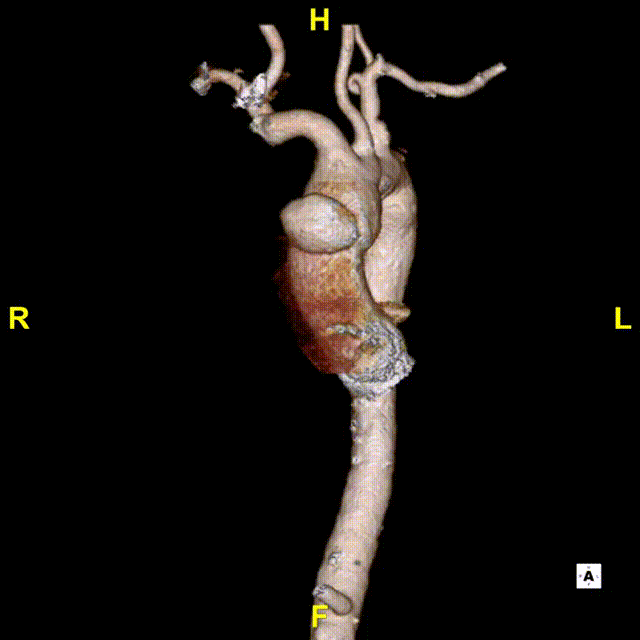

患者入院后行CTA检查,可见患者升主动脉巨大溃疡伴血肿,弓降部多发溃疡。无名动脉前缘至窦管交界大弯侧95.3mm,小弯侧54.7mm。

术前3D重建